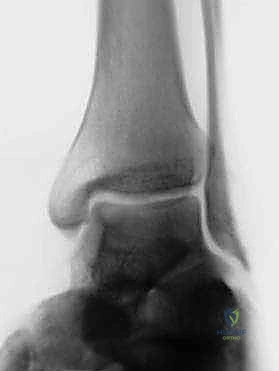

* الأشعة السينية (X-rays): لاستبعاد وجود كسور قديمة غير ملتئمة، أو وجود نتوءات عظمية، وتقييم محور القدم.

* التصوير بالرنين المغناطيسي (MRI): هو المعيار الذهبي. يوضح بدقة متناهية حالة الأربطة (تمزق جزئي، تمزق كلي، أو تندب)، ويساعد في الكشف عن أي إصابات مصاحبة مثل تمزق الأوتار الشظوية أو إصابات الغضروف المفصلي (Osteochondral Lesions).